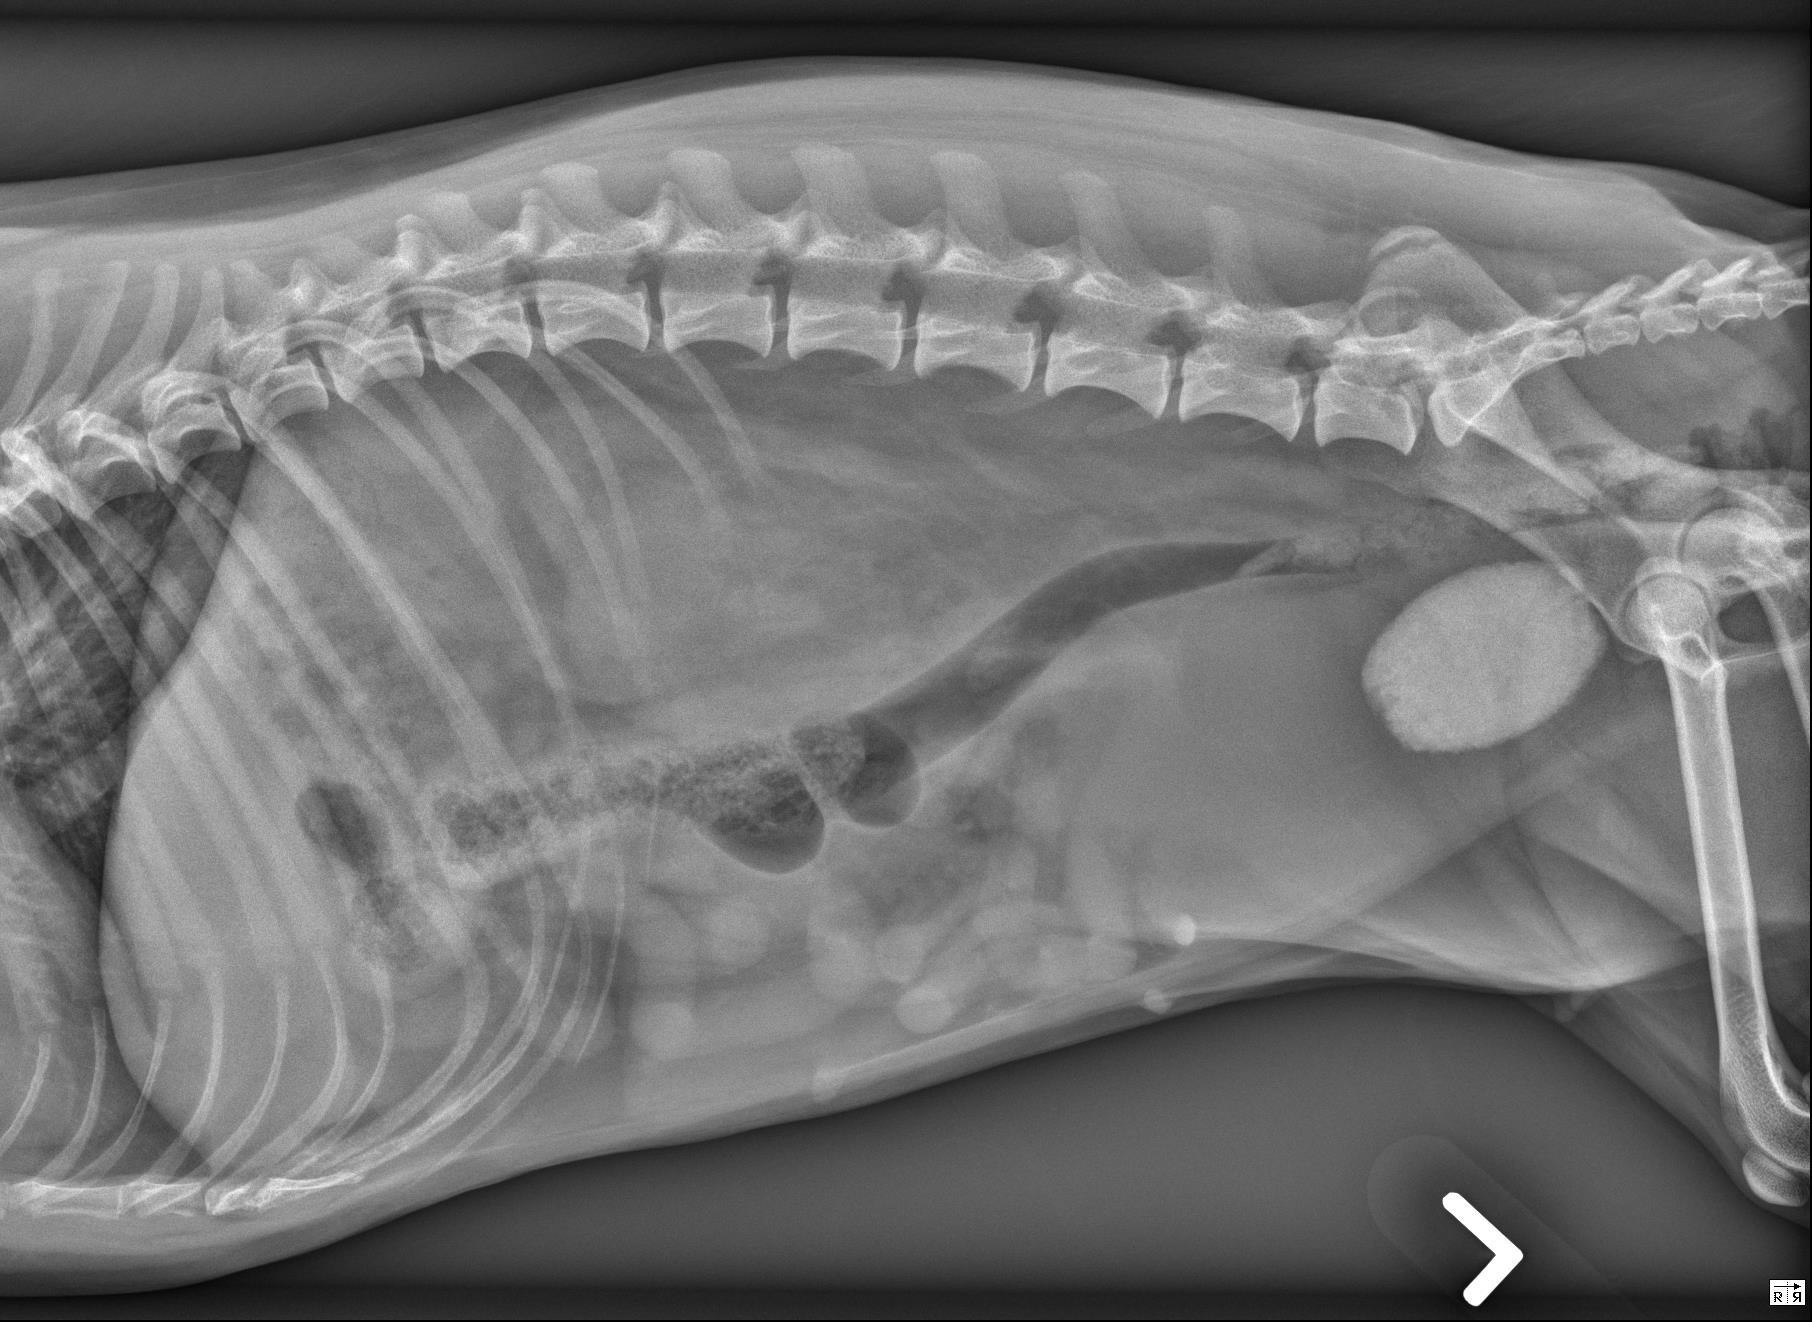

Hieronder vind je de 3 Röntgen foto’s van het abdomen. Gebruik de pijltjes om erdoor te schuiven, of klik op de foto om te vergroten.

Het retroperitoneale detail is aanzienlijk verminderd, met vloeistof-opaque strepen die de niergrenzen verdoezelen. Het peritoneale serosale detail is licht verminderd in de caudale buik, langs de craniale rand van de urineblaas.

Er is een grote, ovale, mineraal-opaque structuur net craniaal van de bekkenopening, in de regio van het trigonum van de urineblaas/proximaal van de urethra, met licht onregelmatige randen (3,6 cm in lengte en 2,5 cm in diameter). De urineblaas is matig tot sterk gedilateerd en homogeen vloeistof-opaque. De lever, milt en het maag-darmkanaal zijn normaal.

Het T8 wervellichaam is verkort en wigvormig.